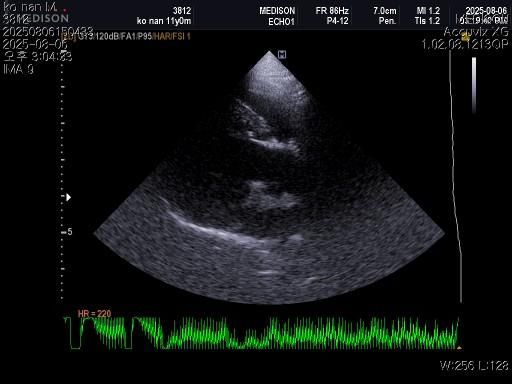

강아지 혈뇨의 원인을 찾고 있습니다 저희 강아지 두번도 아니고 딱 한번만 살려주세요..

1) 혈액검사와 엑스레이 그리고 초음파상 혈뇨의 원인이 나타나지가 않는지 궁금합니다.

2) 그리고 전립선 비대가 있는지도 없는지 여부가 궁금합니다.

3) 신장결석이 어느정도인지도 궁금합니다.

4) 양쪽 부신의 크기가 궁금합니다.

5) 지방간이 있는지 있으면 어느정도인지 궁금합니다..